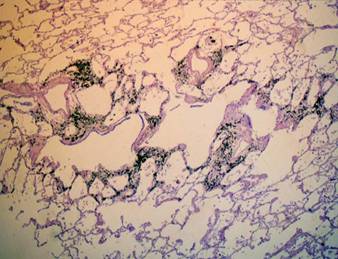

L'immagine radiografica dell'enfisema (Fig. 2) si caratterizza per la presenza di tre reperti 7 [6]:

campi polmonari ipertrasparenti o aree focali di ipertrasparenza, dovute alla distruzione del parenchima polmonare (di difficile identificazione).

appiattimento del diaframma, aumento dello spazio retrosternale e sterno incurvato anteriormente, spazi intercostali slargati e orizzontali

presenza di bolle

Fig. 2: Immagine TC di polmone enfisematoso

Nell'enfisema panlobulare, che interessa prevalentemente i lobi inferiori, i segni radiologici dell'iperinsufflazione sono particolarmente evidenti con l'eccezione delle forme lievi il cui quadro radiologico può essere negativo. Nelle forme più progredite si sovrappongono costantemente i quadri dell'ipertensione precapillare e del cuore polmonare. Nell'enfisema centrolobulare, tipico dei fumatori e che interessa prevalentemente i lobi superiori, i segni radiologici dell'iperinsufflazione sono variabili. Il disegno polmonare è caratteristicamente accentuato con vasi a contorni irregolari e sfumati (endoarterite obliterante e fibrosi perivasale). E' però accertato che l'accentuazione del disegno è in rapporto soprattutto a una dilatazione dei rami vasali (la componente broncogena avrebbe minore importanza). L'enfisema parasettale interessa selettivamente le zone adiacenti alla pleura parietale e mediastinica ed è responsabile della formazione di bolle che possono anche rompersi nello spazio pleurico dando origine ad un pneumotorace [7].